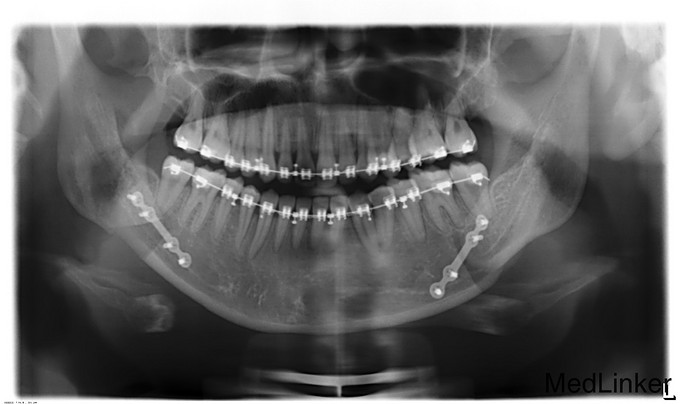

下颌前突十余年。青年女患者,慢性病程。患者于十余年前无明显诱因开始出现下颌前突,于去年11月份开始接受正畸治疗,2015-07-26入我院准备行正颌手术治疗,因感冒出院,今为进一步治疗来我院就诊,门诊以"下颌前突"收入院

面部发育良好,左右基本对称,上中下比例协调,面下三分之一过长前突左偏,颏顶点左偏,双侧颞下颌关节无弹响无疼痛,开口度3.7cm,开口型正常,上下牙弓关系不协调,中线不齐,前牙反牙合,后牙近中错牙合,左侧后牙反牙合,龋齿无,牙周病无。

诊断:下颌前突,全麻下行“双侧下颌升支矢状劈开后退术+双侧下颌骨去骨皮质术+双侧下颌骨骨内坚固内固定术+双侧邻近瓣转移修复术”,术后予消炎、消肿等对症治疗。

患者主要是单颌畸形,单纯运用矢状劈开就可以,不动上颌